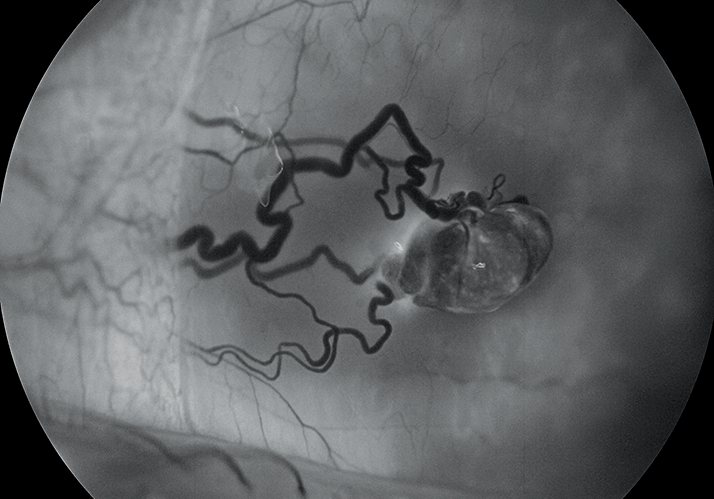

Fluorescein angiogram of a pyogenic granuloma at 5 minutes, 40 seconds on a 30-year-old male with a complaint of left eye irritation with no vision loss. The conjunctival hemangioma was 1 mm from plica and 5 mm from the limbus (nasal). The conjunctival lesion was later removed during surgery (excisional biopsy and cryo) and the patient made a full recovery.